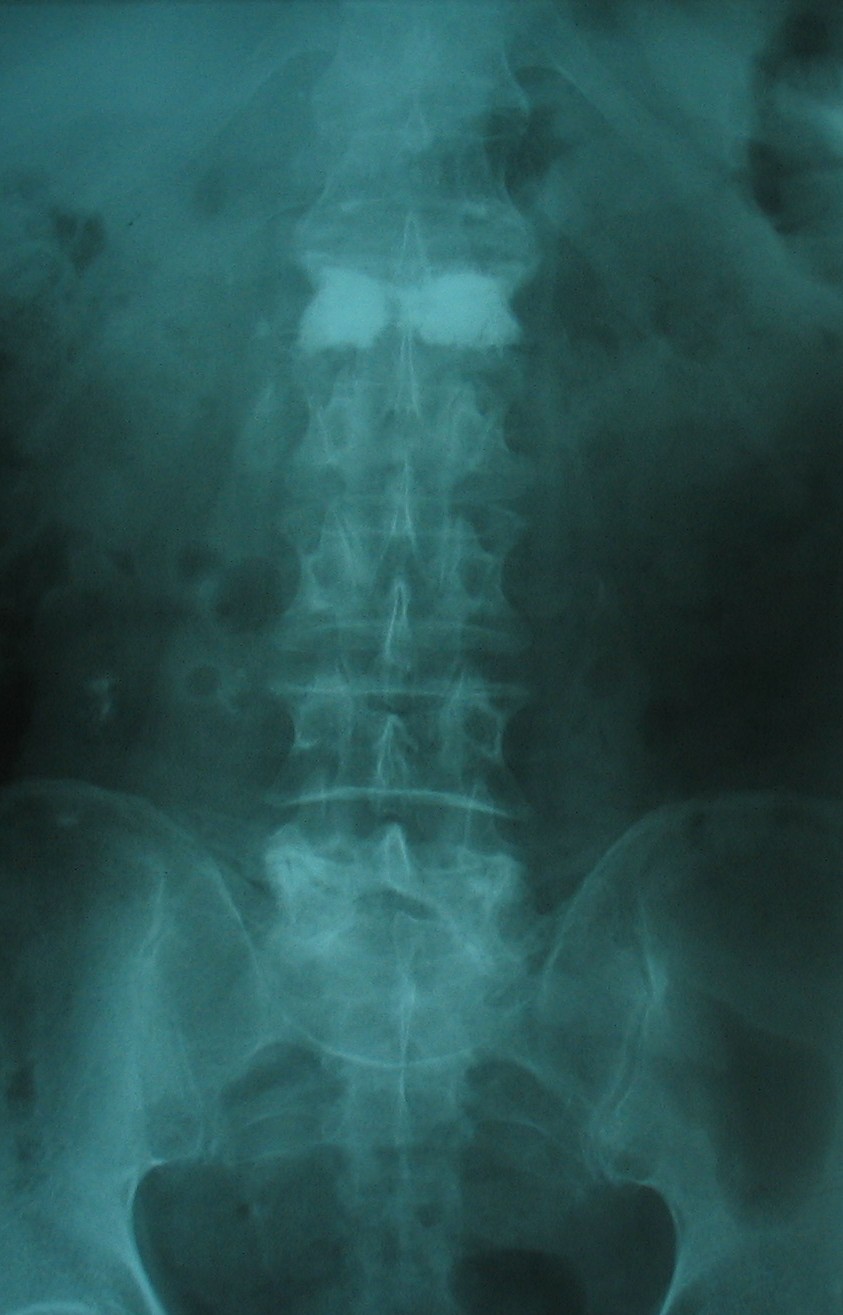

Kemik erimesine (osteoporoza) bağlı omurga kırığı olan hastada vertebroplasti (çimento ile dolgu) tedavisi